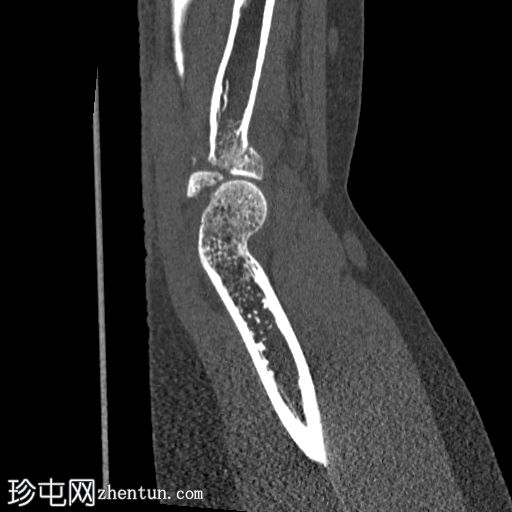

矢状面骨窗

显示整个桡骨头粉碎性骨折,特征为两个以上大骨折块,以及倾斜且受压的关节节。

这表明该骨折为不稳定骨折,根据Mason桡骨头骨折分型,为IIIC型。

远端肱骨和可见尺骨未见骨折征象。

此外,由于关节积血导致关节扩张,肘关节脂肪平面弯曲。